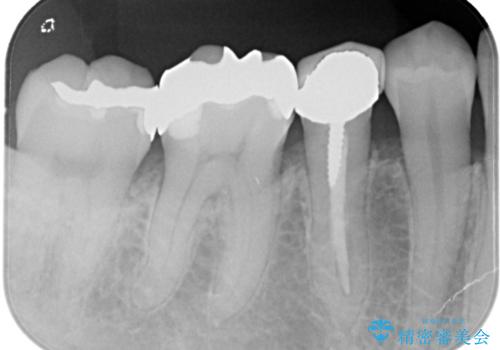

- 笑った時に見える金属を白くしたいとのことでメタルフリーの治療を希望され来院されました。

根管治療を行なったのち、オールセラミッククラウンにて修復処置を行っております。